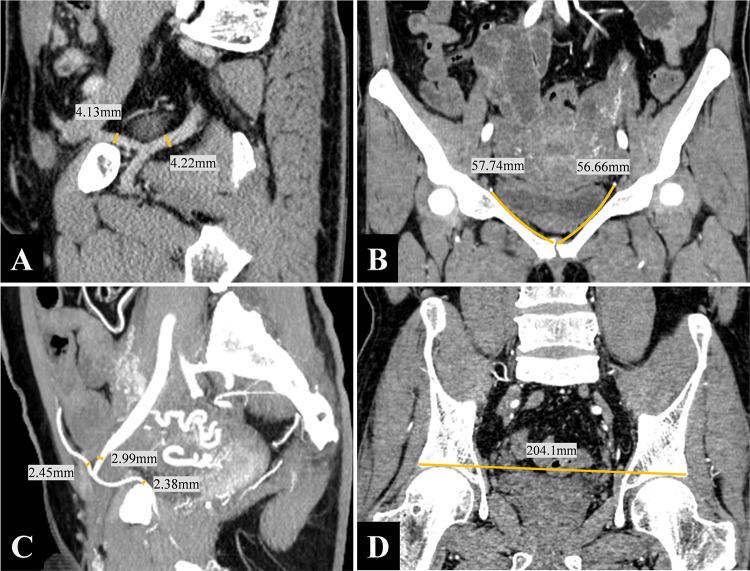

To analyze CT angiographic images to provide comprehensive data on the corona mortis (CMOR) and propose a new classification method for venous corona mortis (VCMOR). This retrospective study included 719 patients (378 males, mean age 55 years) who underwent CT-enhanced examination of the whole abdomen or pelvis. Patient demographics, variation incidence, vessel diameter and location, anatomical configuration, and acetabular distance were evaluated. 73.44% of patients had at least one arterial or venous CMOR, with bilateral occurrences being more common (P < 0.001). The incidence of arterial corona mortis (ACMOR) was 23.92%, and it could be categorized into four types. The mean distance from ACMOR to the pubic symphysis was 56.6 mm, with a greater distance in females (62.2 mm) compared to males (50.4 mm) (P < 0.001). The incidence of VCMOR was 68.43%, with a higher bilateral occurrence (P < 0.001). Fourteen anatomical configurations of the VCMOR were identified and classified into two types and five subtypes. The mean interacetabular distance was 200.5 mm. The origin and branching variation of CMOR vary considerably, especially the venous type, which is characterized by diversity and complexity and needs to be recognized before pelvic operation.

分析CT血管造影图像,以提供关于死亡冠(CMOR)的全面数据,并提出一种新的静脉死亡冠(VCMOR)分类方法。这项回顾性研究纳入了719例接受全腹或盆腔CT增强检查的患者(378例男性,平均年龄55岁)。评估了患者的人口统计学特征、变异发生率、血管直径和位置、解剖结构以及髋臼距离。73.44%的患者至少有一处动脉或静脉CMOR,双侧出现更为常见(P<0.001)。动脉死亡冠(ACMOR)的发生率为23.92%,可分为四种类型。ACMOR到耻骨联合的平均距离为56.6mm,女性(62.2mm)比男性(50.4mm)距离更远(P<0.001)。VCMOR的发生率为68.43%,双侧出现率更高(P<0.001)。确定了VCMOR的14种解剖结构,并分为两种类型和五个亚型。髋臼间平均距离为200.5mm。CMOR的起源和分支变异差异很大,尤其是静脉型,其特点是多样和复杂,在盆腔手术前需要识别。